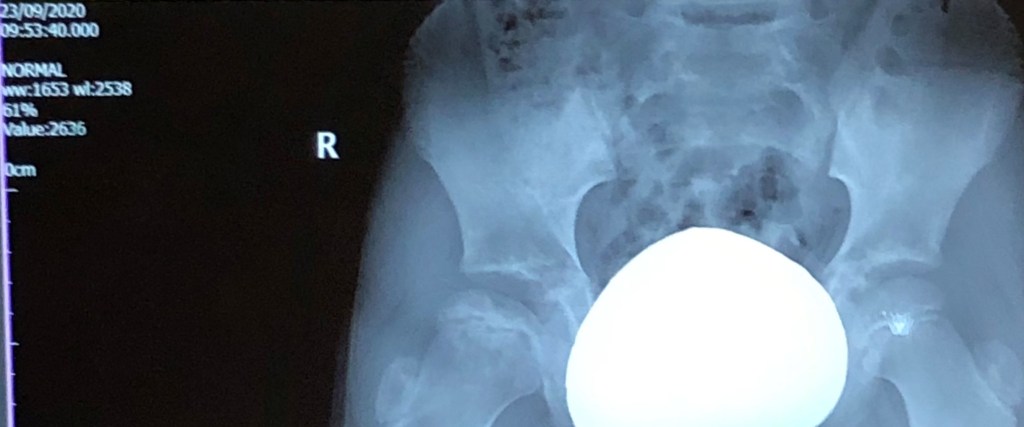

The below scans show his right (bad) hip joint compared to his left (good), and a comparison view of his right hip between Nov 2019 and September 2020. Hard to see with the untrained eye, but combined with what the Consultant tells us, we believe we can see it looking more dense, more rounded, and less black stuff!

September 2020 x-ray showing right (bad) hip compared to left (good) hip.

Comparing November 2019 to September 2020

How it looked November 2017 during the collapse / fragmentation stage